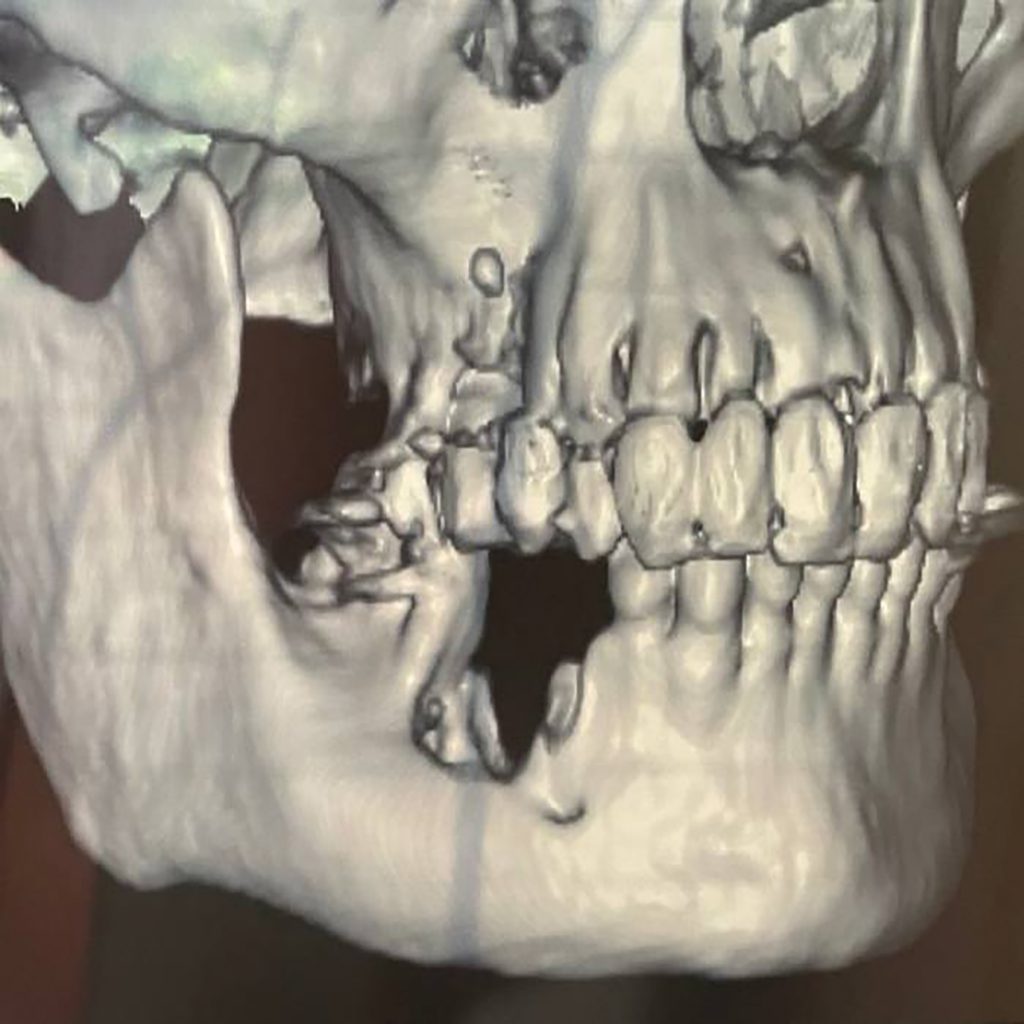

Surgical Orthodontic Procedures | Enhancing Orthodontic Outcomes

Aligning precision and beauty , where surgery meets symmetry